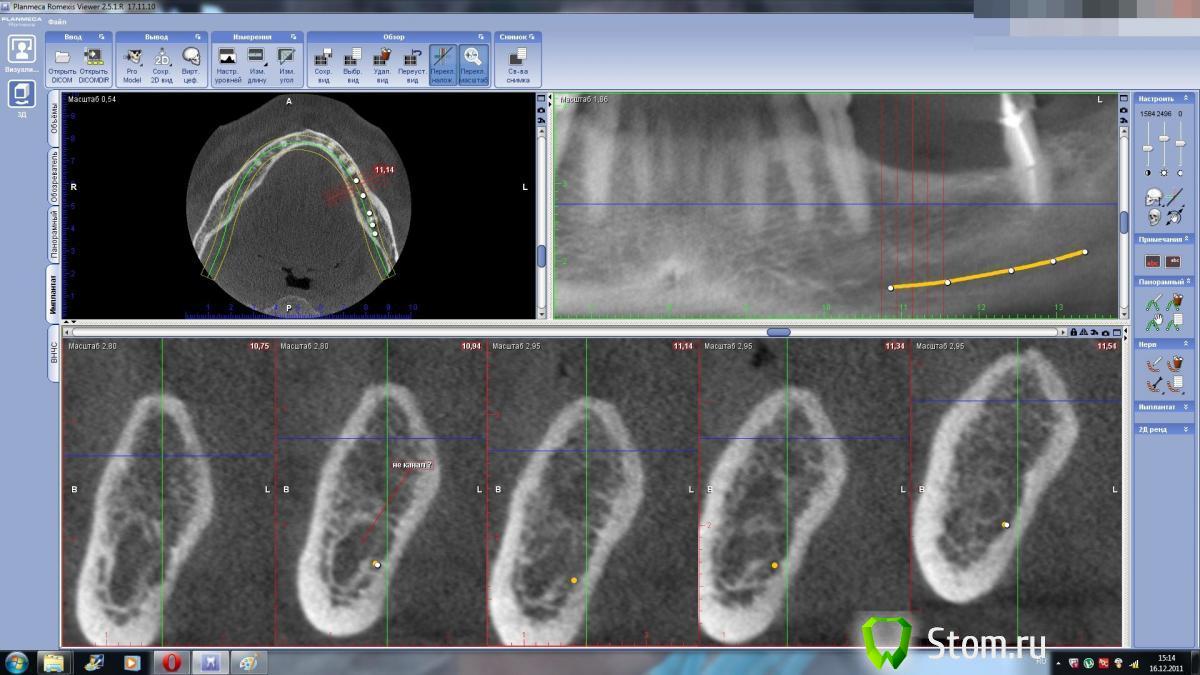

dent-a Опубликовано 16 декабря, 2011 Поделиться Опубликовано 16 декабря, 2011 Есть ли критерии hu для нижнечелюстного канала. Что то сомневаюсь по КТшке где канал и как следствие- расстояние до него. Может есть у кого светлые мысли или опыт.спасибо. Ссылка на комментарий

Bier Опубликовано 16 декабря, 2011 Поделиться Опубликовано 16 декабря, 2011 а в чем проблема? пятно то темное хорошо просматривается Ссылка на комментарий

merson Опубликовано 16 декабря, 2011 Поделиться Опубликовано 16 декабря, 2011 очень хорошо видно -Bier прав -темное пятно на срезах неправильной формы ближе к основанию челюсти Ссылка на комментарий

dent-a Опубликовано 16 декабря, 2011 Автор Поделиться Опубликовано 16 декабря, 2011 а в чем проблема? пятно то темное хорошо просматриваетсяЭм....может я туплю, но сможете в пэйнте - пометить верх и низ канала на вертикальных срезах.Я что то не могу определиться с глубиной формирования ложа.Спасибо. Ссылка на комментарий

kriokov Опубликовано 16 декабря, 2011 Поделиться Опубликовано 16 декабря, 2011 Для меня тоже проблема. Я так увидел. Ссылка на комментарий

dent-a Опубликовано 16 декабря, 2011 Автор Поделиться Опубликовано 16 декабря, 2011 Для меня тоже проблема. Я так увидел.Я так же разглядел (при таком положении канал уходит выше "проекции канала" на панорамных срезах на пару мм.).Человек в возрасте, адентия не первый день, есть склероз канала. Ссылка на комментарий

Bier Опубликовано 16 декабря, 2011 Поделиться Опубликовано 16 декабря, 2011 не рискуйте, поставьте по короче винты Ссылка на комментарий

dent-a Опубликовано 17 декабря, 2011 Автор Поделиться Опубликовано 17 декабря, 2011 не рискуйте, поставьте по короче винтыОк., спасибо, тоже склоняюсь к этому. Ссылка на комментарий